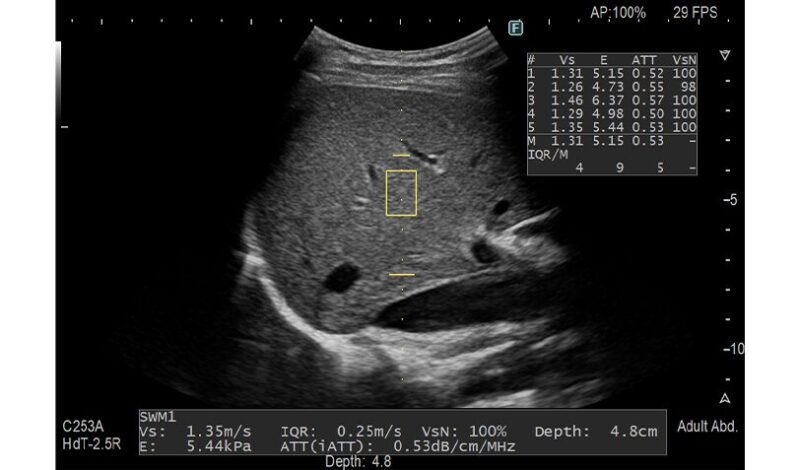

当院では、これまでも多くの肝障害や脂肪肝の診療をおこなってまいりましたが、この度富士フィルムのARIETTA 650というエコーで、実際に脂肪肝の程度と肝硬変の評価に使う肝硬度を測定できるようになりました。

エコーの画像での評価だけではなく、実際に数値として評価、比較を行う事ができるようになります。

今回の検査でそれをエコーと同時に5分程度で、脂肪肝の程度、肝硬度(繊維化の具合)を同時はかることができるため、注意が必要な方を負担が少なく発見することができます。